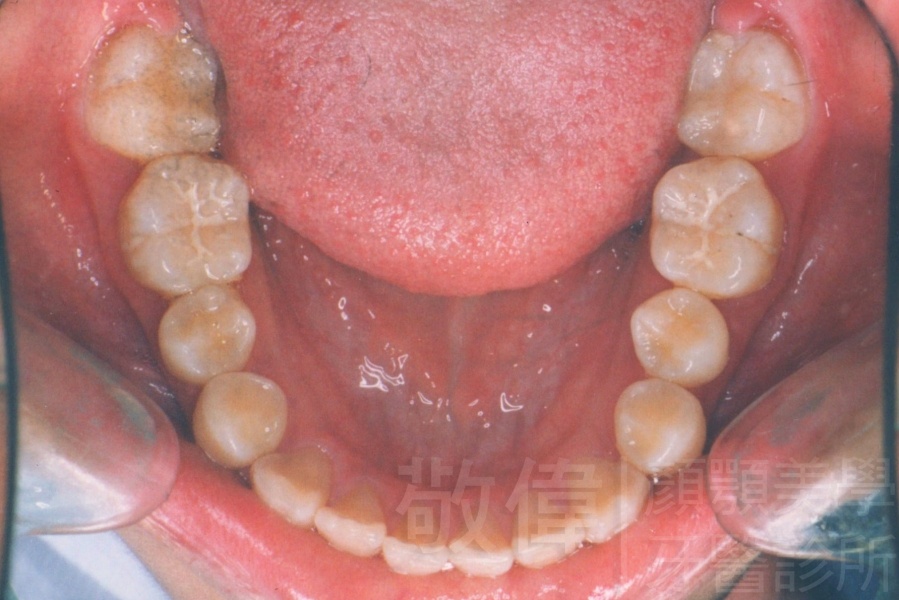

齒顏矯正/變臉矯正-月亮妹 變身 陽光正妹

變臉矯正,原來戽斗妹跟大歪臉變成自信正妹

經由本院3D數影X光影像儀分析、與3D齒顎顏矯正技術,再配合口腔顎面正顎專科醫師施以正顎手術治療,雙方共同合作,使患者臉部外觀有很好的改善,大歪變小歪,產生了天南地北的大改變,她的人生也整個變得不一樣。

因為矯正與正顎手術的配合,使「戽斗妹」變成了「陽光正妹」,完全的改變了她的人生,在面對各種場合、與人交際都散發出自信微笑。所以,奉勸家長,如果小朋友有臉顎畸型的問題,應該考慮配合做這種簡單、安全、有效的正顎手術。

「3D齒顎顏矯正」,不止矯正您的牙齒,也會改變您的人生。「治療前」和「治療後」出社會的人生際遇一定會截然不同。